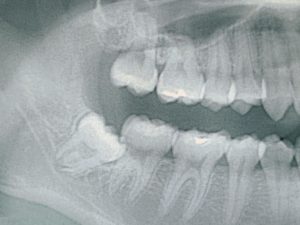

2020年7月25日 研修ブログ 2021年8月31日 丸子歯科 豊田市の丸子歯科 講習会「レントゲンの読み方セミナー」 こんにちは。豊田市丸子歯科スタッフの永井です。 令和2年7月19日に丸子歯科の待合室にて ZOOMでのセミナーに参加させて頂きました。 セミナーの内容はレントゲンによる診査です。 歯医者には「痛みが出たら行こう」「虫歯になったら行こう」と思…